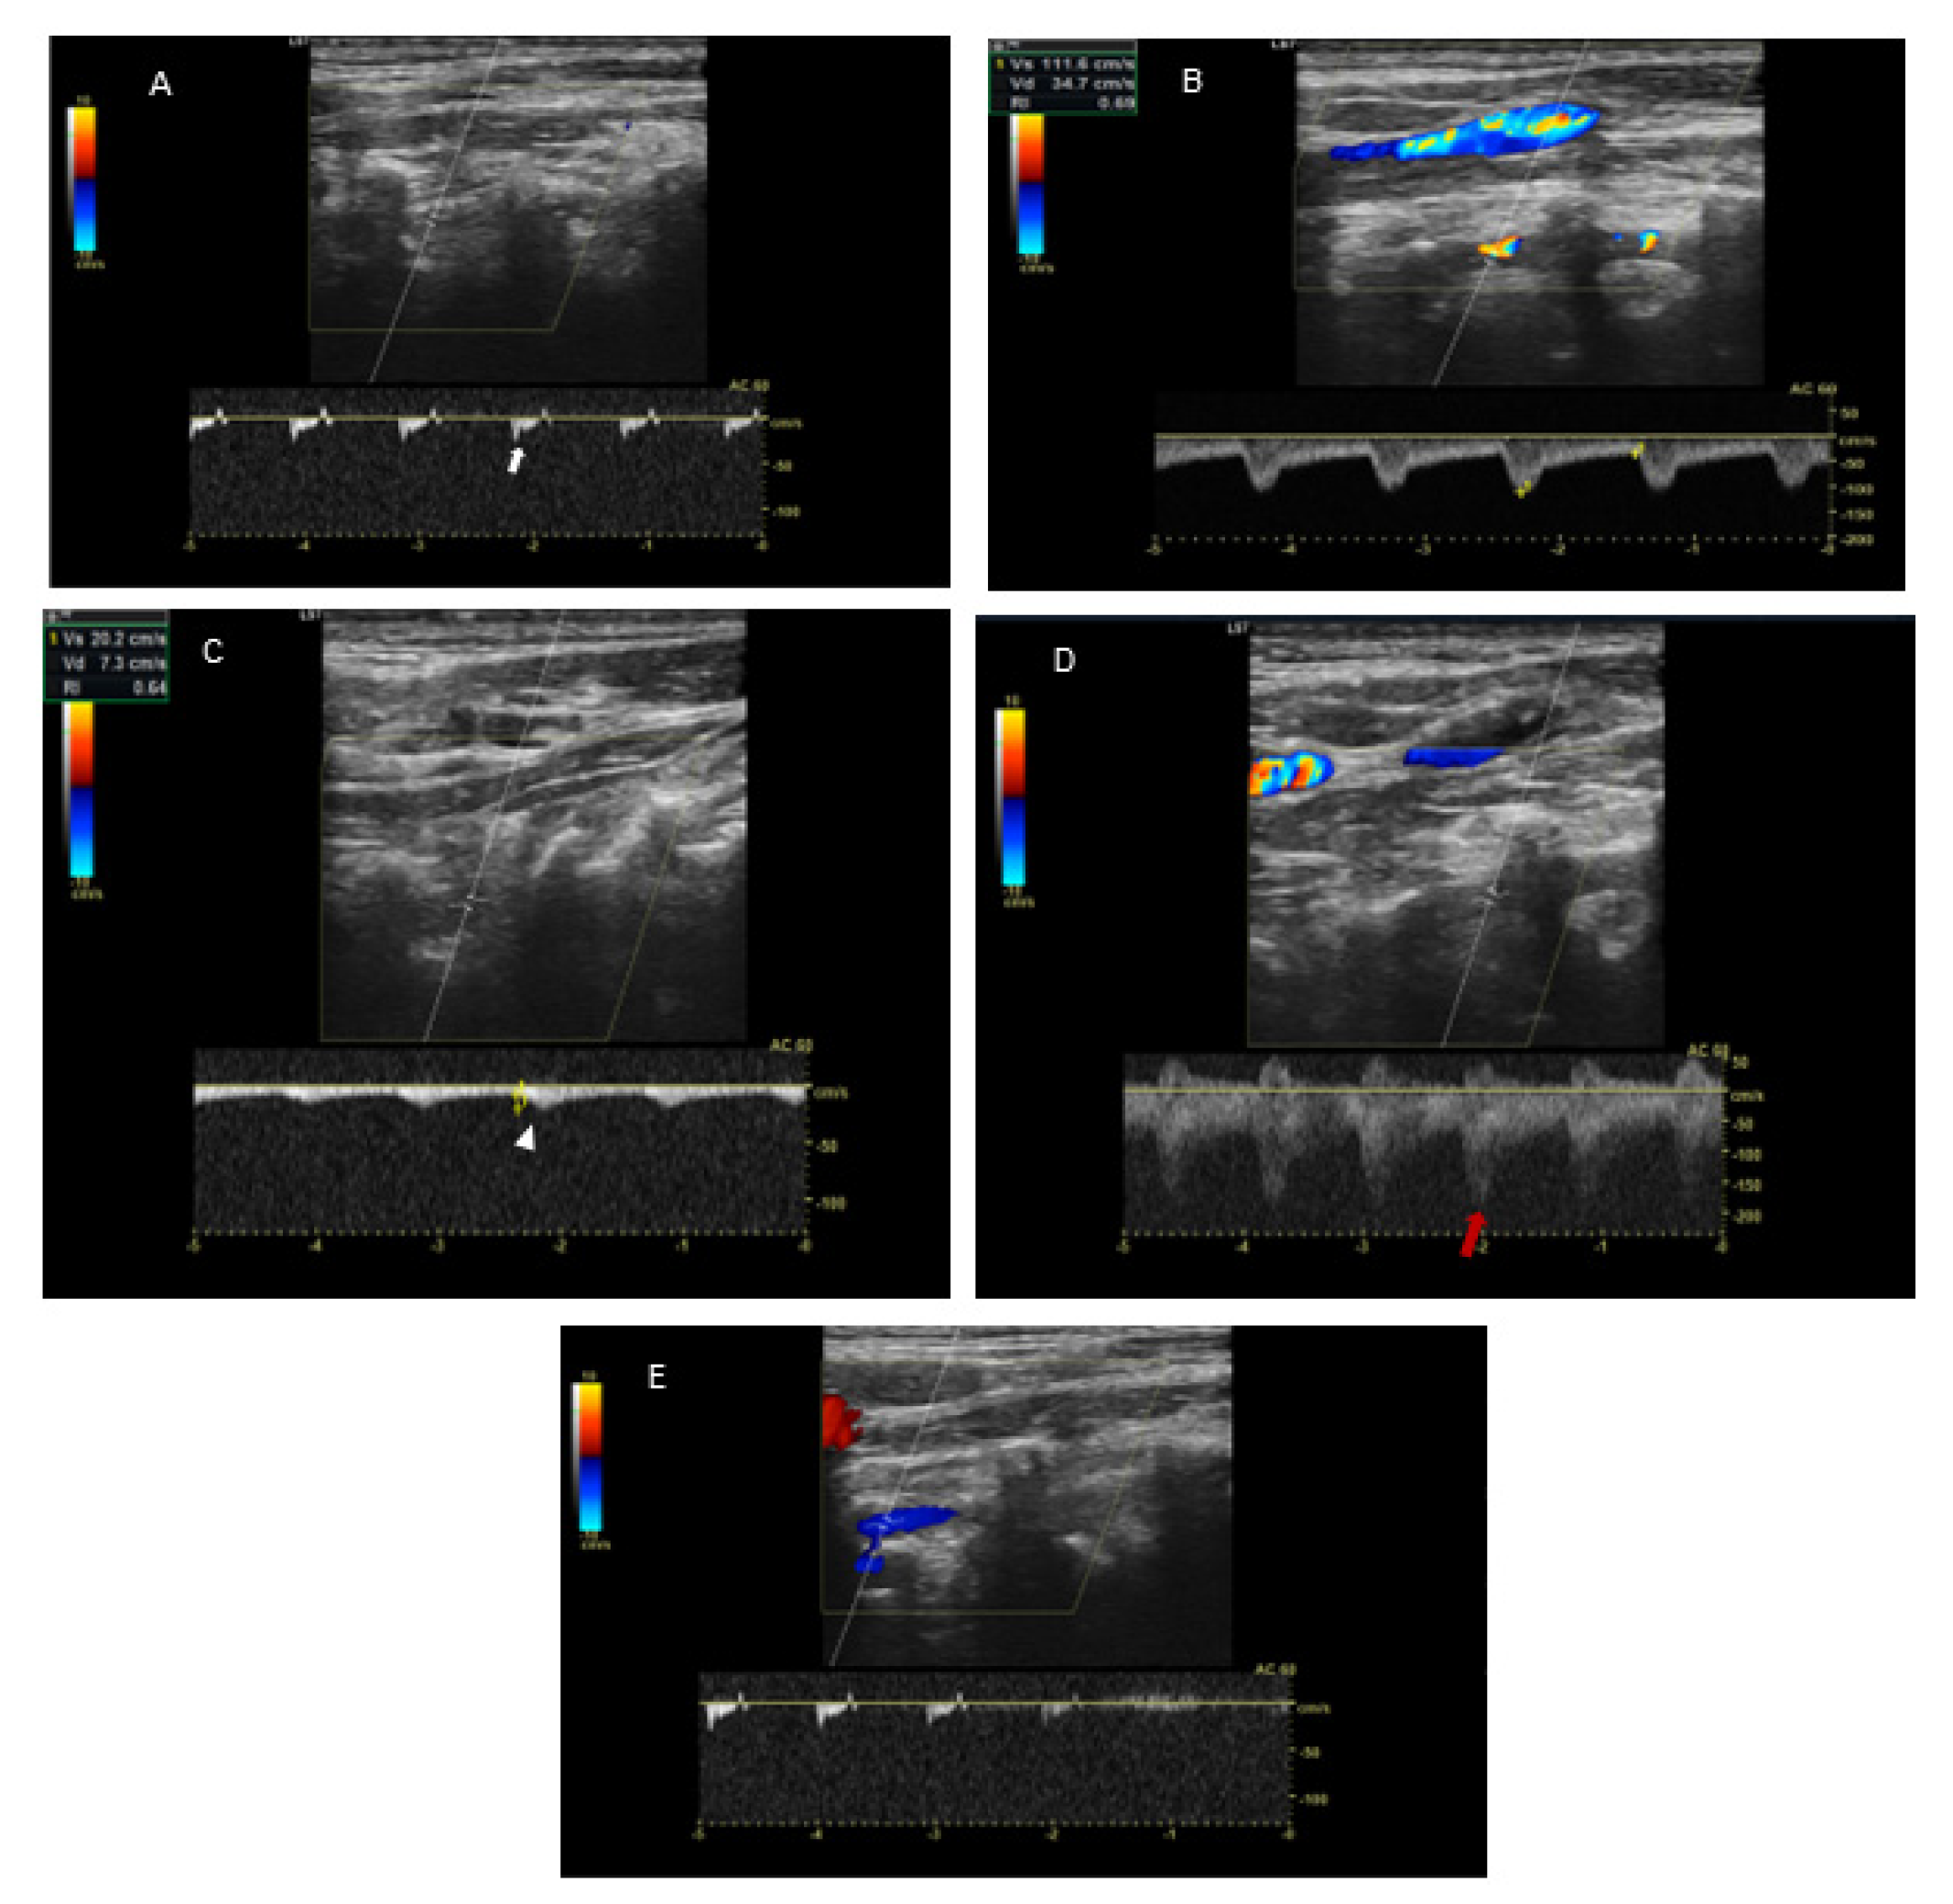

Because of the suspected dynamic stenosis, a dynamic CT angiography (D-CTA) of the carotid, vertebral and cerebral arteries was performed. Firstly, the imaging was conducted with the patient’s head in the neutral position. It revealed atheromatous plaques in both carotid bulbs (slightly calcified; maximum thickness: 2.8 mm) with no hemodynamically significant stenosis, grade 2 of kinking of R-ICA and a tortuosity of L-ICA. Furthermore, hypoplasia of R-VA was demonstrated (widths: R-VA 1.9 mm; L-VA 3.6 mm). L-VA had a tortuous course and it formed a loop at the level of the C4 vertebrae. There was no L-VA stenosis in this position (Figure 2A). Subsequently, D-CTA was acquired during left-side rotation of the head. In this examination the lumen of L-VA was narrowed up to 2 × 3.2 mm, causing 60% stenosis according to the NASCET criteria (Figure 2B) [7]. 3D reconstructions of this pathology were also obtained (Figure 3A,B). It was also observed that basilar artery (BA) was formed exclusively by L-VA. No abnormalities of other cerebral arteries were observed.

Figure 2. Dynamic CT angiography in the neutral head position and left-side rotation. Panel (A): Axial D-CTA in the neutral head position demonstrates L-VA loop in V2 segment (red arrow) at C4 level and R-VA hypoplasia (red arrowhead). No L-VA stenosis in this position. Panel (B): Axial D-CTA in left-side head rotation demonstrates the narrowing of L-VA lumen (up to 2 mm × 3.2 mm) that causes a dynamic 60% L-VA stenosis in the loop at C4 level (red arrow).